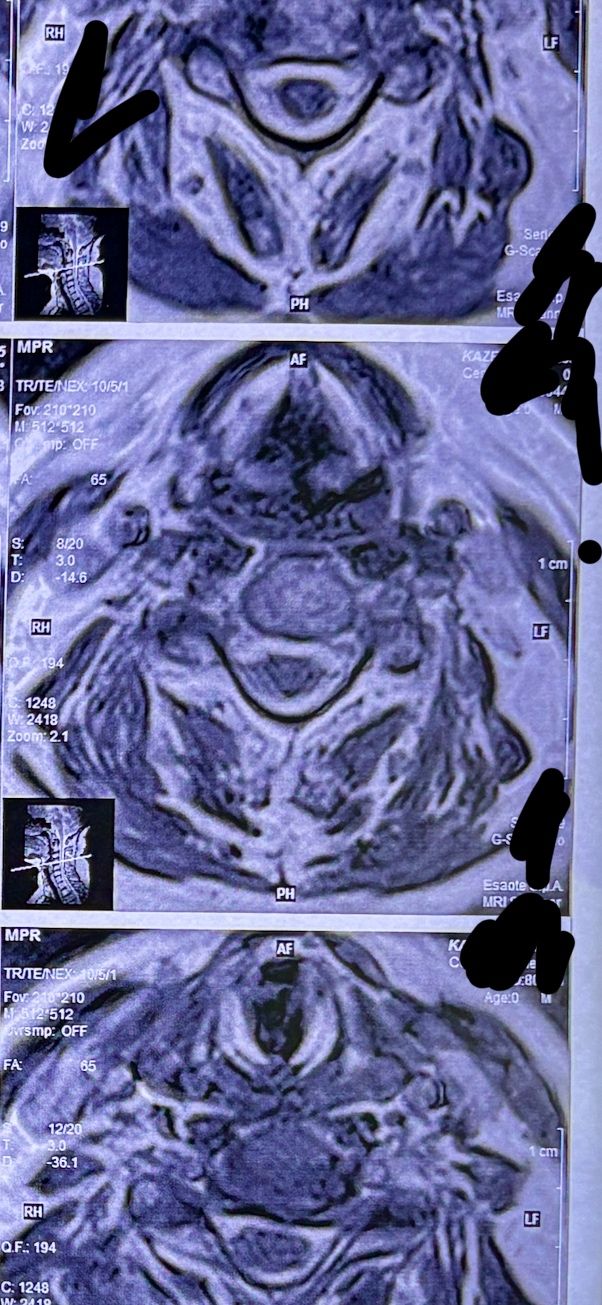

41 years old man presented to my clinic in October 2023 with acute and sever R neck pain with radicular pain to his R upper extremity along C6 dematom since 2 weeks ago. Examination didn’t show any upper motor signs. Was suggested urgent surgery

I ordered EMG/ NCV : showed mild R C6, C7 irritation without any active axonal loss

In his MRI was reported R. para R. IVF Massive extrusion. I decided to control his pain and manage this patient with reevaluation of patient every other session. For 5 sessions i just used acupuncture and laser and IFC and mild adjustments to his R. T3-T7 and mild arthosteem to above and below involved segment. Cervical adjustment considered contraindicated for this patient. From session 6th- 8th i started to use mild/gentle cervical decompression. He used soft cervical collar all the time. His pain decreased by 80 percent

I gave him cervical traction pump to be used 3-5 times per day at home for the next 3 months and i released the patient. He was evaluated every week once for one month and after that every 2 weeks. After 3 month I repeated MRI. Size of the herniated disc was reduced greater than 50 percent. Asked him to do another mri in 6 months

MRIs before and after proper management of this patient: